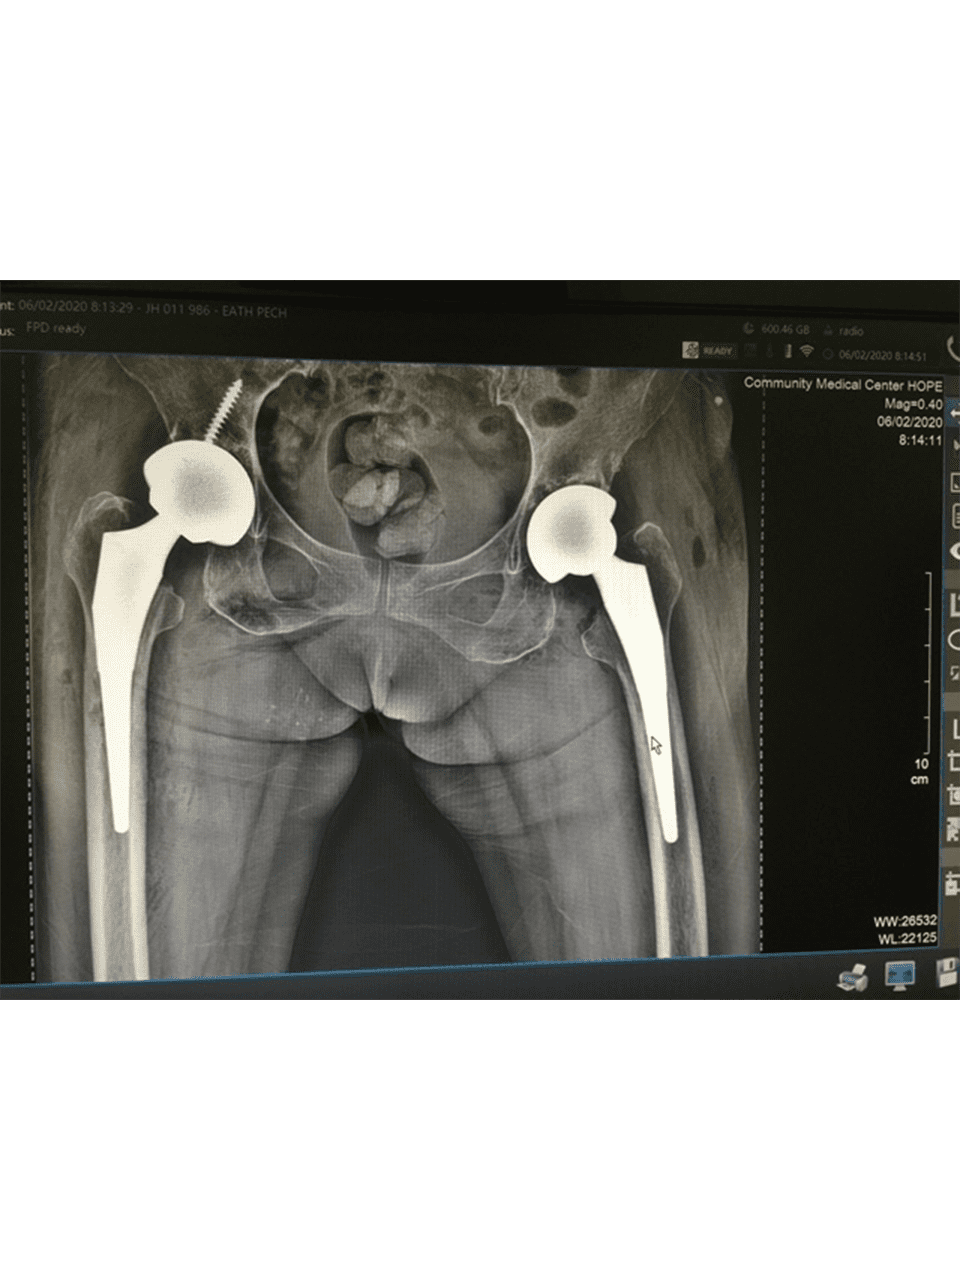

Dr. Weber and his partners participate in short term medical mission trips to Cambodia. Dr. Weber has had the pleasure of going twice now in 2018 and 2020. During these trips Dr. Weber performs total hip replacements on patients who normally would have no treatment options. To learn more and to see videos from the experience please click the links below.